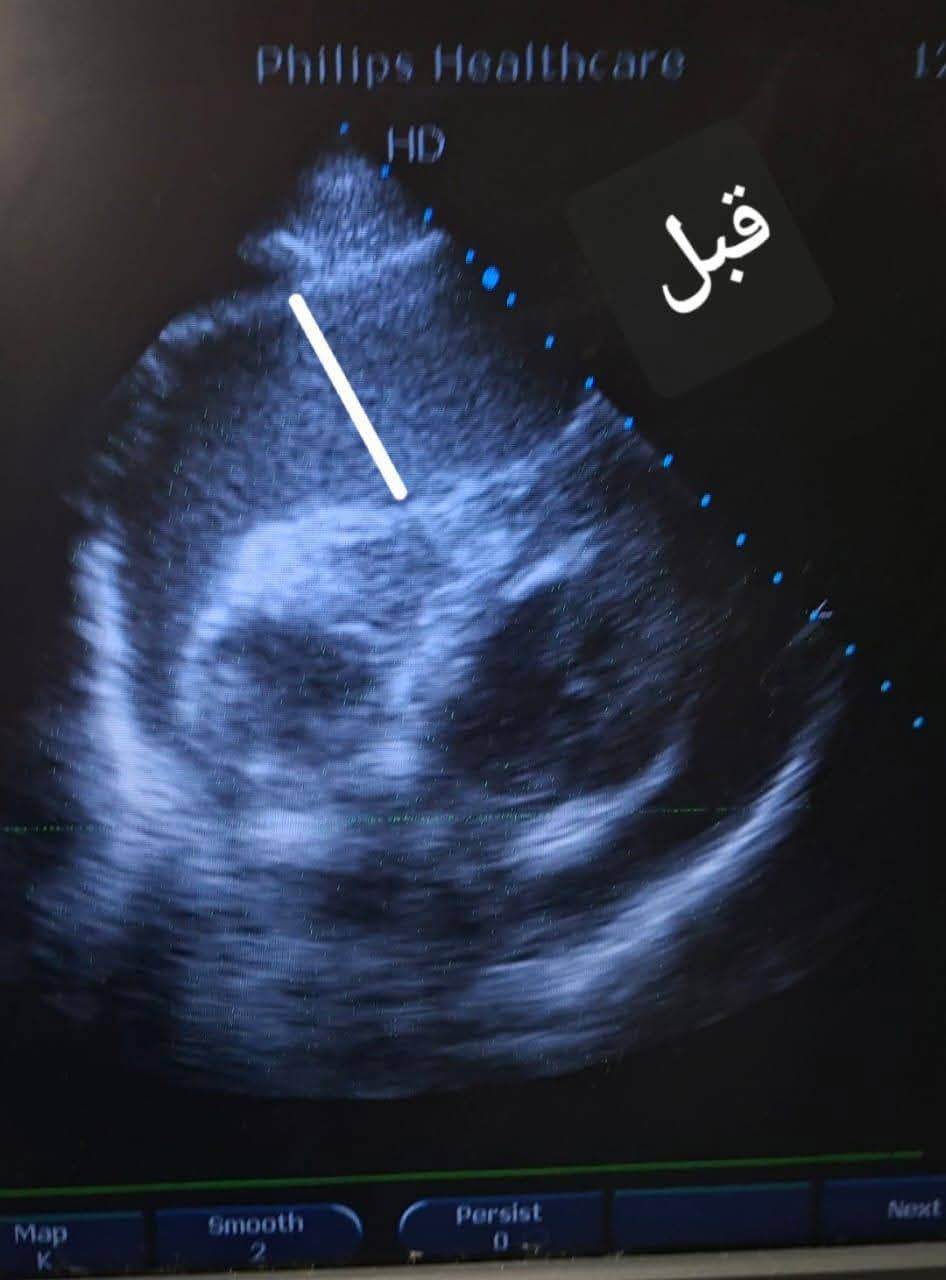

ومع المتابعة الدقيقة والمرور الطبي المنتظم، لاحظ الأطباء ارتفاعًا حادًا في معدل نبضات القلب، ما استدعى تحركًا فوريًا وإجراء رسم قلب كهربائي (ECG) وفحص الموجات الصوتية على القلب (Echocardiography)، لتكشف الفحوصات عن ارتشاح بالغشاء التاموري مصحوب بتأثير ضاغط على عضلة القلب، وهي حالة حرجة تتطلب تدخلًا عاجلًا دون أي تأخير.

وخلال ثوان معدودة، جرى التنسيق السريع مع قسم قسطرة القلب، حيث تولّى الفريق الطبي بقيادة الدكتور أحمد صبحي المدرس بالقسم، وبمشاركة الدكتور عبدالرحمن أحمد الخطيب الأخصائي، تجهيز الحالة ونقلها بشكل عاجل، ليتم تنفيذ بذل فوري للغشاء التاموري (Pericardiocentesis) داخل قسم القسطرة، في أول إجراء من نوعه يُنفذ بالقسم منذ إنشائه.

وأسفر التدخل الدقيق والسريع عن سحب ما يقرب من 700 مل من السوائل من الغشاء التاموري، وهو ما انعكس مباشرة على الحالة العامة للمريض، حيث ارتفعت نسبة تشبع الأكسجين واستقرت العلامات الحيوية بصورة ملحوظة، في مشهد جسّد بوضوح قيمة القرار الطبي السريع المبني على خبرة علمية وتكامل مهني.